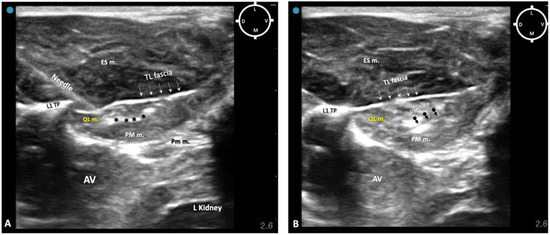

To overcome this complication, on the other two of four rabbits scheduled for the sono-anatomy and quadratus lumborum block design phase, the needling was performed using a modified dorsolateral approach as reported recently in dogs by Viscasillas and colleagues (2021), in which the needle passed through the epaxial muscles and a medial injection site was performed in the quadratus lumborum fascia, between the QL and PM muscles. This avoided visceral contamination with dye solution in these remaining two rabbits. For this reason, in the present study, only the dorsal approach was subsequently used (Figure 3).

Figure 3. Sono-anatomy of the thoracolumbar area at the level of the twelfth thoracic vertebra transverse process (T12 TP). The arrows point out the thoraco-lumbar (TL) fascia (dot line). The quadratus lumborum muscle (QL m.) is located ventral to the transverse process and the TL fascia and dorsal to the psoas major muscle (PM m.). The injection point for the ultrasound-guided quadratus lumborum block is within the quadratus lumborum fascia the hyperechoic line separating the PM m. and the QL m (yellow dot line). AV abdominal viscera; D dorsal; ES m. erector spinae muscles; L lateral; M medial; Pm m. psoas minor muscle; V ventral; T12 TP Transverse process of the twelfth thoracic vertebra. Cyan blue dot represents the probe marker pointed in this case dorsally.